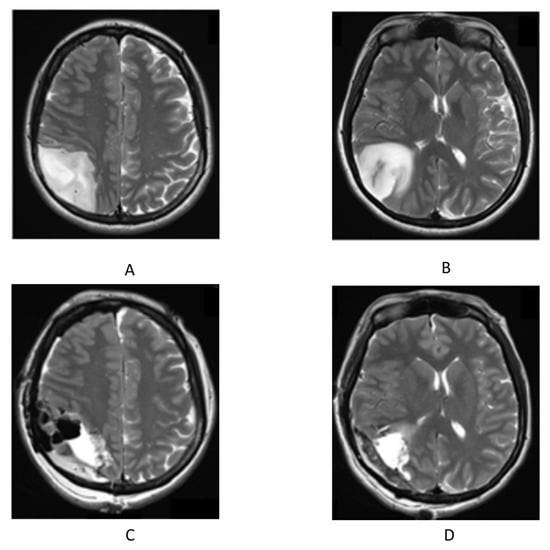

2. Case Presentation

2.1. Initial Evaluation